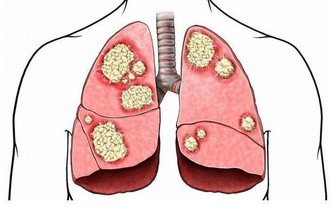

臨床上對癡呆既往病史的研究發現,血管性癡呆占多數,在預防老年癡呆方面,除了要有良好的生活方式外,不妨試試穴位按摩。